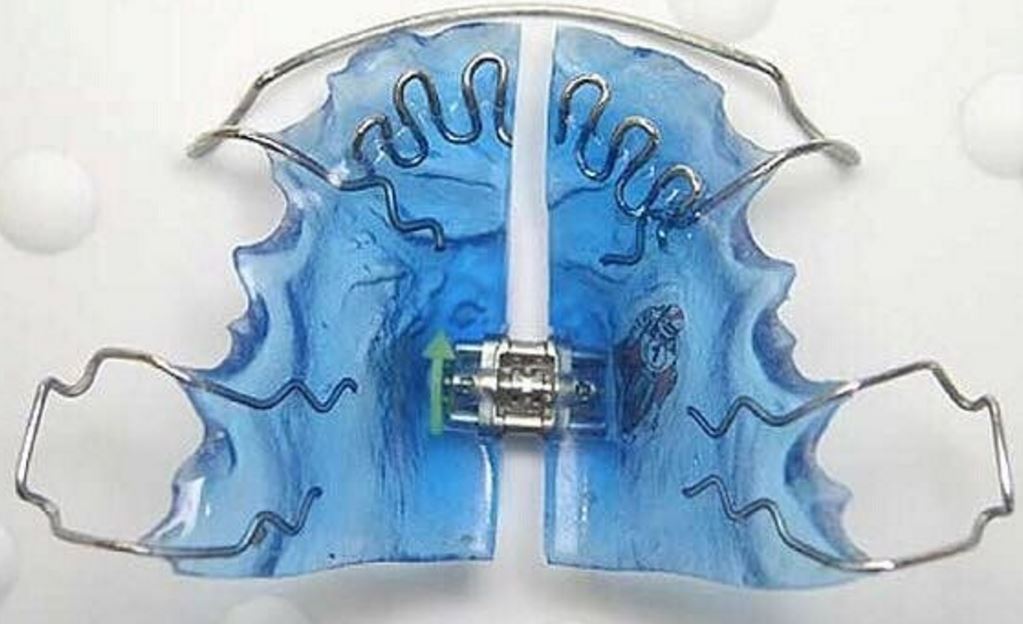

Детские пластинки для исправления прикуса

Что такое детские пластинки

Детские стоматологические пластины для исправления прикуса